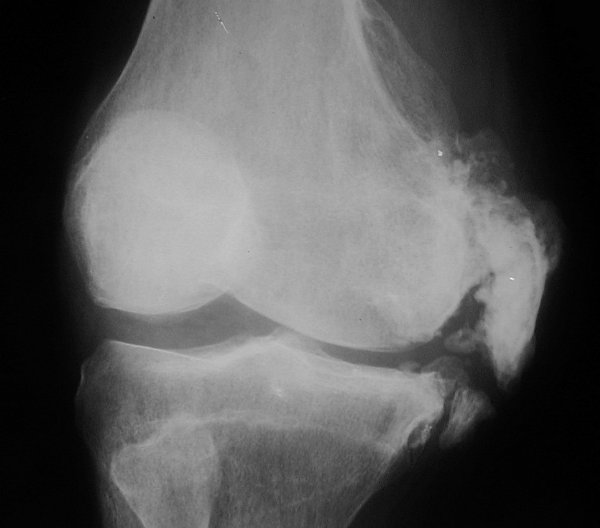

Return to Pelligrini-Stieda Disease